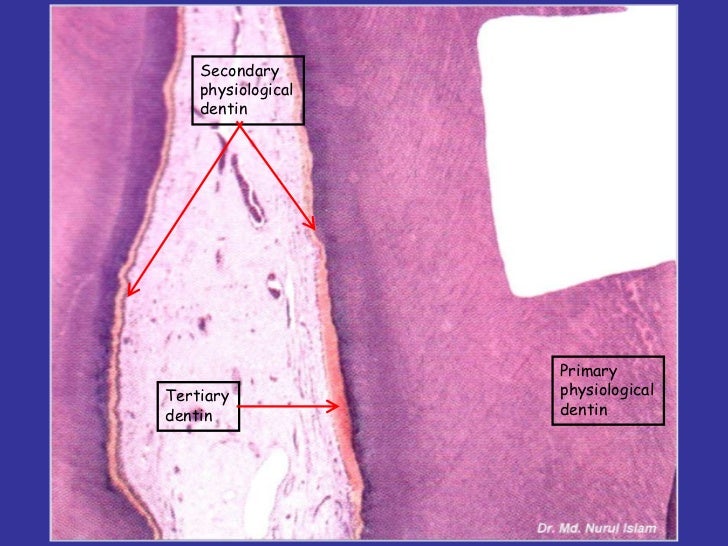

What Is The Difference Between Secondary Dentin And Tertiary Dentin Quizlet . A) secondary dentin forms before the tooth erupts and. three types of dentin exist: dentin is classified into three types: Secondary dentin forms before the tooth erupts and. [ 24 ] [ 25 ] secondary dentin is a layer of dentin. primary dentin forms the body of the tooth; tertiary dentin (including reparative dentin or sclerotic dentin) is a form of dentin, one of the main component materials of teeth. Secondary dentin forms only after tooth eruption and is a narrow band that borders the pulp. Primary dentin, secondary dentin, and tertiary dentin. —primary dentin is defined as all dentin. what is the difference between secondary dentin and tertiary dentin? study with quizlet and memorize flashcards containing terms like what is the difference between secondary dentin and tertiary. what is the difference between secondary dentin and tertiary dentin?